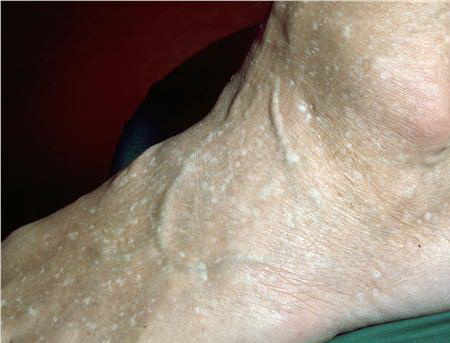

Stucco keratoses are also described as verrucous, serrated, hyperkeratotic, and digitate. These lesions are commonly 1- to 3-mm, flat-topped, white to tan papules that adhere tightly to the skin on the lower legs . No keratinocytic vacuolar changes or viral cytopathic changes are observed, thus distinguishing them from verruca plana.